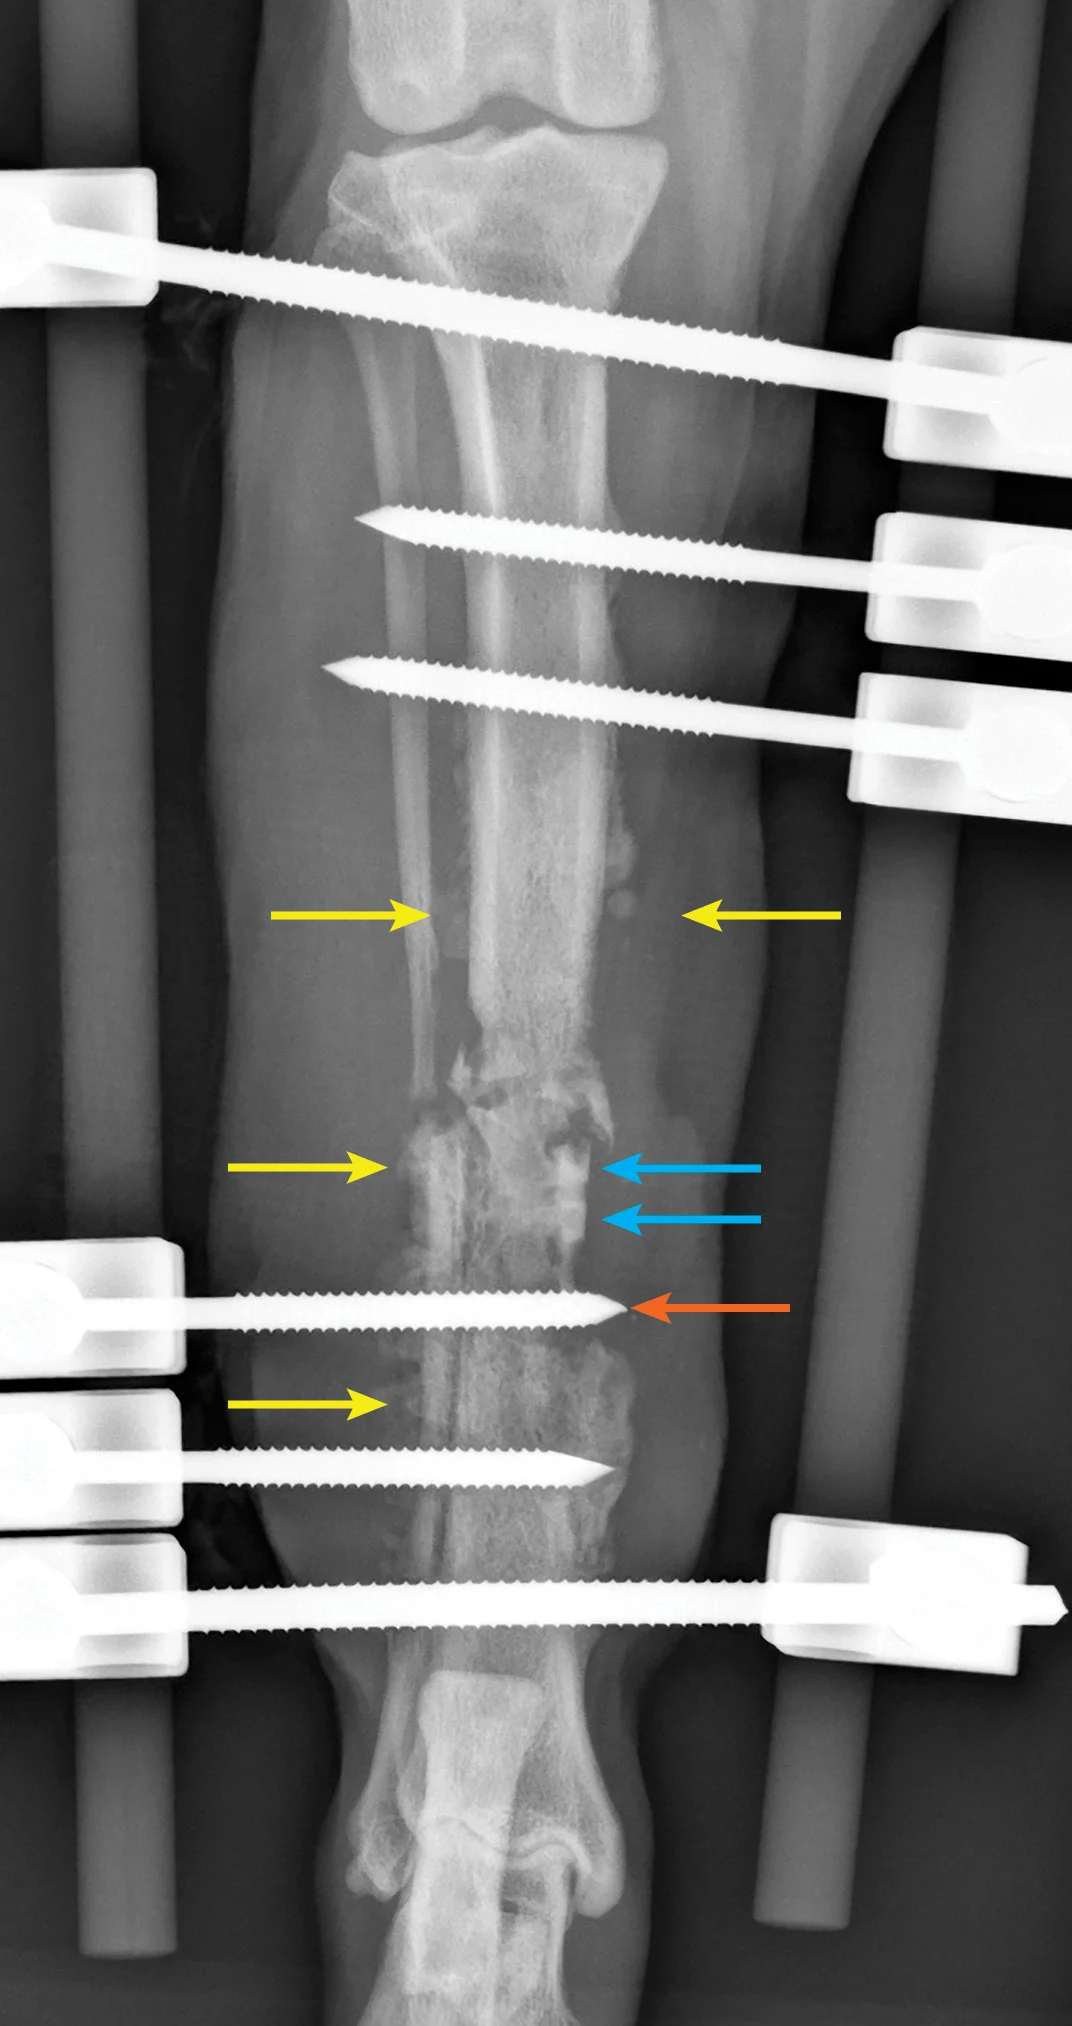

Clindamycin has great bone penetration; however, as a lincosamide antibiotic, it is bacteriostatic and, therefore, should not be given in combination with a bactericidal drug. Clindamycin affects bacteria via inhibition of protein synthesis of the bacterial ribosome and has excellent activity against most pathologic anaerobic bacteria; most aerobic gram-positive cocci (eg, staphylococci, streptococci) are also susceptible. This drug is often effective against Corynebacterium spp, Nocardia asteroides, and Mycoplasma spp. It is FDA-approved for treating osteomyelitis (Figure) in dogs (11-33 mg/kg PO q12h) and cats (11-33 mg/kg PO q24h).13

Craniocaudal radiograph of a postoperative (8 weeks) open tibial fracture with tibial/fibular osteomyelitis. Note the large degree of soft tissue swelling, spiculated periosteal response (yellow arrows), sequestrum (blue arrows), and loose transfixation of the pin on the external skeletal fixator (orange arrow). Successful treatment of this patient’s infection required a multimodal approach including removal of the sequestrum, debridement of necrotic material and biofilm, removal and replacement of the loose transfixation pin, and antibiotics based on culture and susceptibility testing of deep wound tissue.